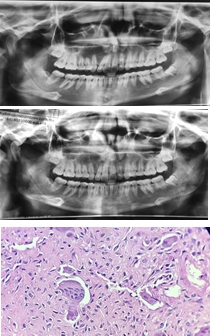

Se presenta paciente femenina de 17 años quien acude a consulta por dolor en cuadrante II. En la Rx panorámica y CBTC se observa área radiolúcida de 2.5cm abarcando desde el OD 2.2 hasta 2.5; cuyo resultado histopatológico resultó GCCG. En base a la evidencia científica, se decide tratar la lesión de manera no quirúrgica debido al compromiso de OD y la extensión de la misma. Se realizaron 8 infiltraciones intralesionales de triamcinolona combinada con lidocaína durante 8 semanas. En radiografías de control se observa resolución de la lesión.

El tratamiento quirúrgico puede resultar en defectos óseos no deseados, es debido a esto que la infiltración intralesional con corticoesteroides es un tratamiento efectivo y conservador otorgando la resolución o reducción del tamaño de la lesión de manera que permita una remoción quirúrgica conservadora, preservando estructuras adyacentes.